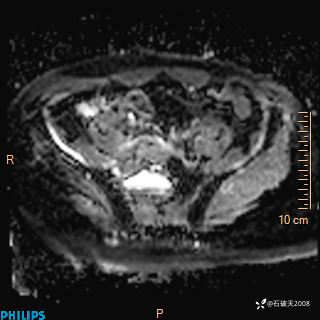

2023年3月份MRI影像

增强轴位